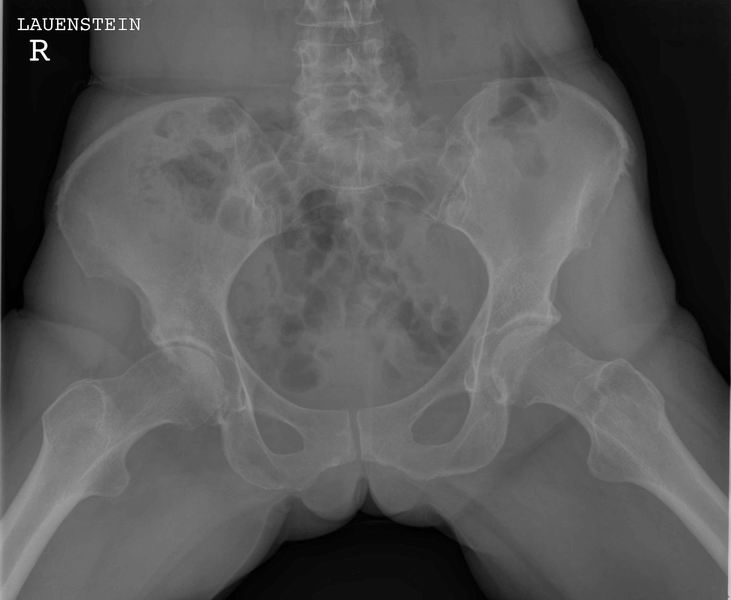

Bekken